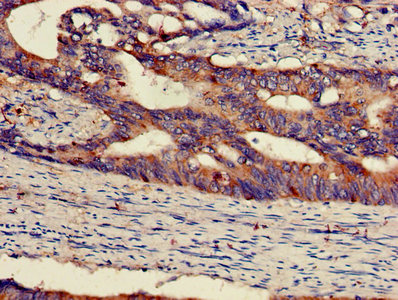

IHC (Immunohiostchemistry)

(IHC image of AAA232572 diluted at 1:300 and staining in paraffin-embedded human colon cancer performed on a Leica BondTM system. After dewaxing and hydration, antigen retrieval was mediated by high pressure in a citrate buffer (pH 6.0). Section was blocked with 10% normal goat serum 30min at RT. Then primary antibody (1% BSA) was incubated at 4 degree C overnight. The primary is detected by a biotinylated secondary antibody and visualized using an HRP conjugated SP system.)